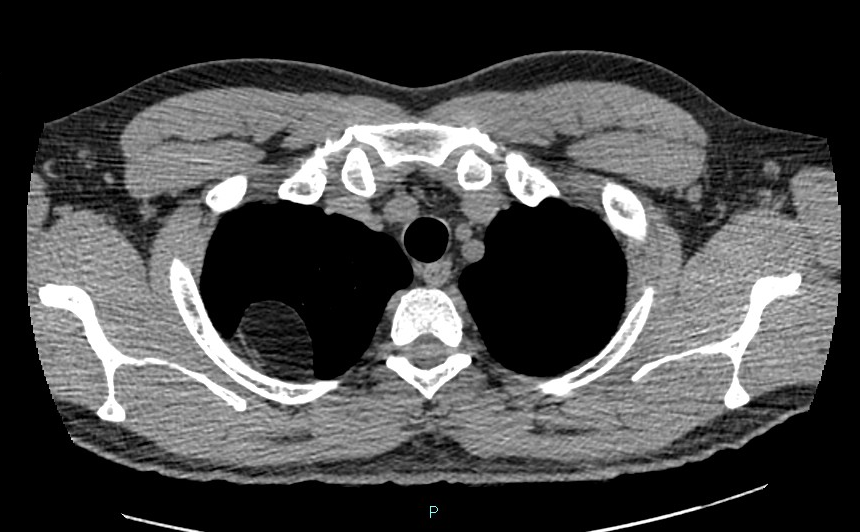

A TCAR (HRCT) de tórax demonstra acentuado espessamento septal nas regiões subpleurais de ambos os pulmões, com múltiplas bandas subpleurais e foco de atelectasia arredondada no segmento basal posterior do lobo inferior direito. Os achados são compatíveis com asbestose.